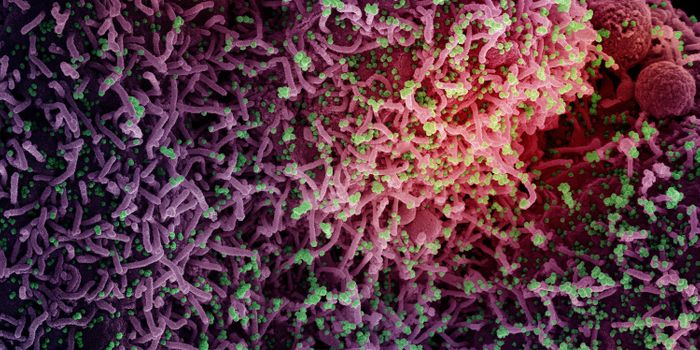

AUG 19, 2020Cell & Molecular BiologyAs the pandemic virus, SARS-CoV-2 continues to cause tens of thousands of new cases of COVID-19 every day in the United ...

APR 27, 2020MicrobiologyThe pandemic virus that causes COVID-19 has now infected nearly 3 million people, and killed over 200,000.

MAY 10, 2021MicrobiologyThe pandemic virus SARS-CoV-2 has changed the world in devastating ways, taking hundreds of thousands of lives & new var ...